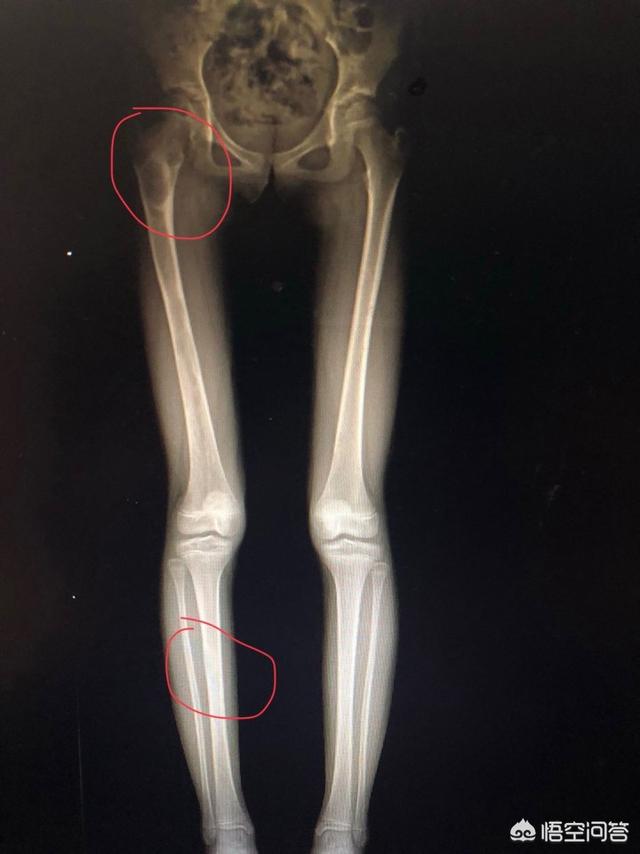

Cas 2 : Il s'agit presque d'un diagnostic manqué. Un frère de 40 ans, d'âge moyen, souffre d'une douleur à la jambe. J'ai posé des questions sur les antécédents et vérifié le corps, et j'ai pensé qu'il s'agissait d'un léger claquage. Mais le patient a demandé à faire une radiographie des membres inférieurs en pied, la raison est que son ami fait de la rééducation, il a dit que ses membres inférieurs n'étaient pas de la même longueur, pour lui donner une semelle de rehaussement à la même longueur, les explications répétées sont inefficaces, OK, tirez ! Résultat, le numéro suivant est toujours le sien, sa fille a cinq ans, plus puissante, sans aucune gêne, aussi son ami lui a dit de faire une semelle de chaussure, encore une fois les explications répétées ne sont pas valables, OK, tirez !

Un regard qui donne des sueurs froides :

Les adultes vont bien, les enfants ont de multiples malstructures fibreuses des membres inférieurs, des tumeurs bénignes et des accidents évités de justesse ! Même si le patient dit que tout va bien, le médecin examinera les tests effectués. Il s'agit également d'un mécanisme de prévention et de réparation.